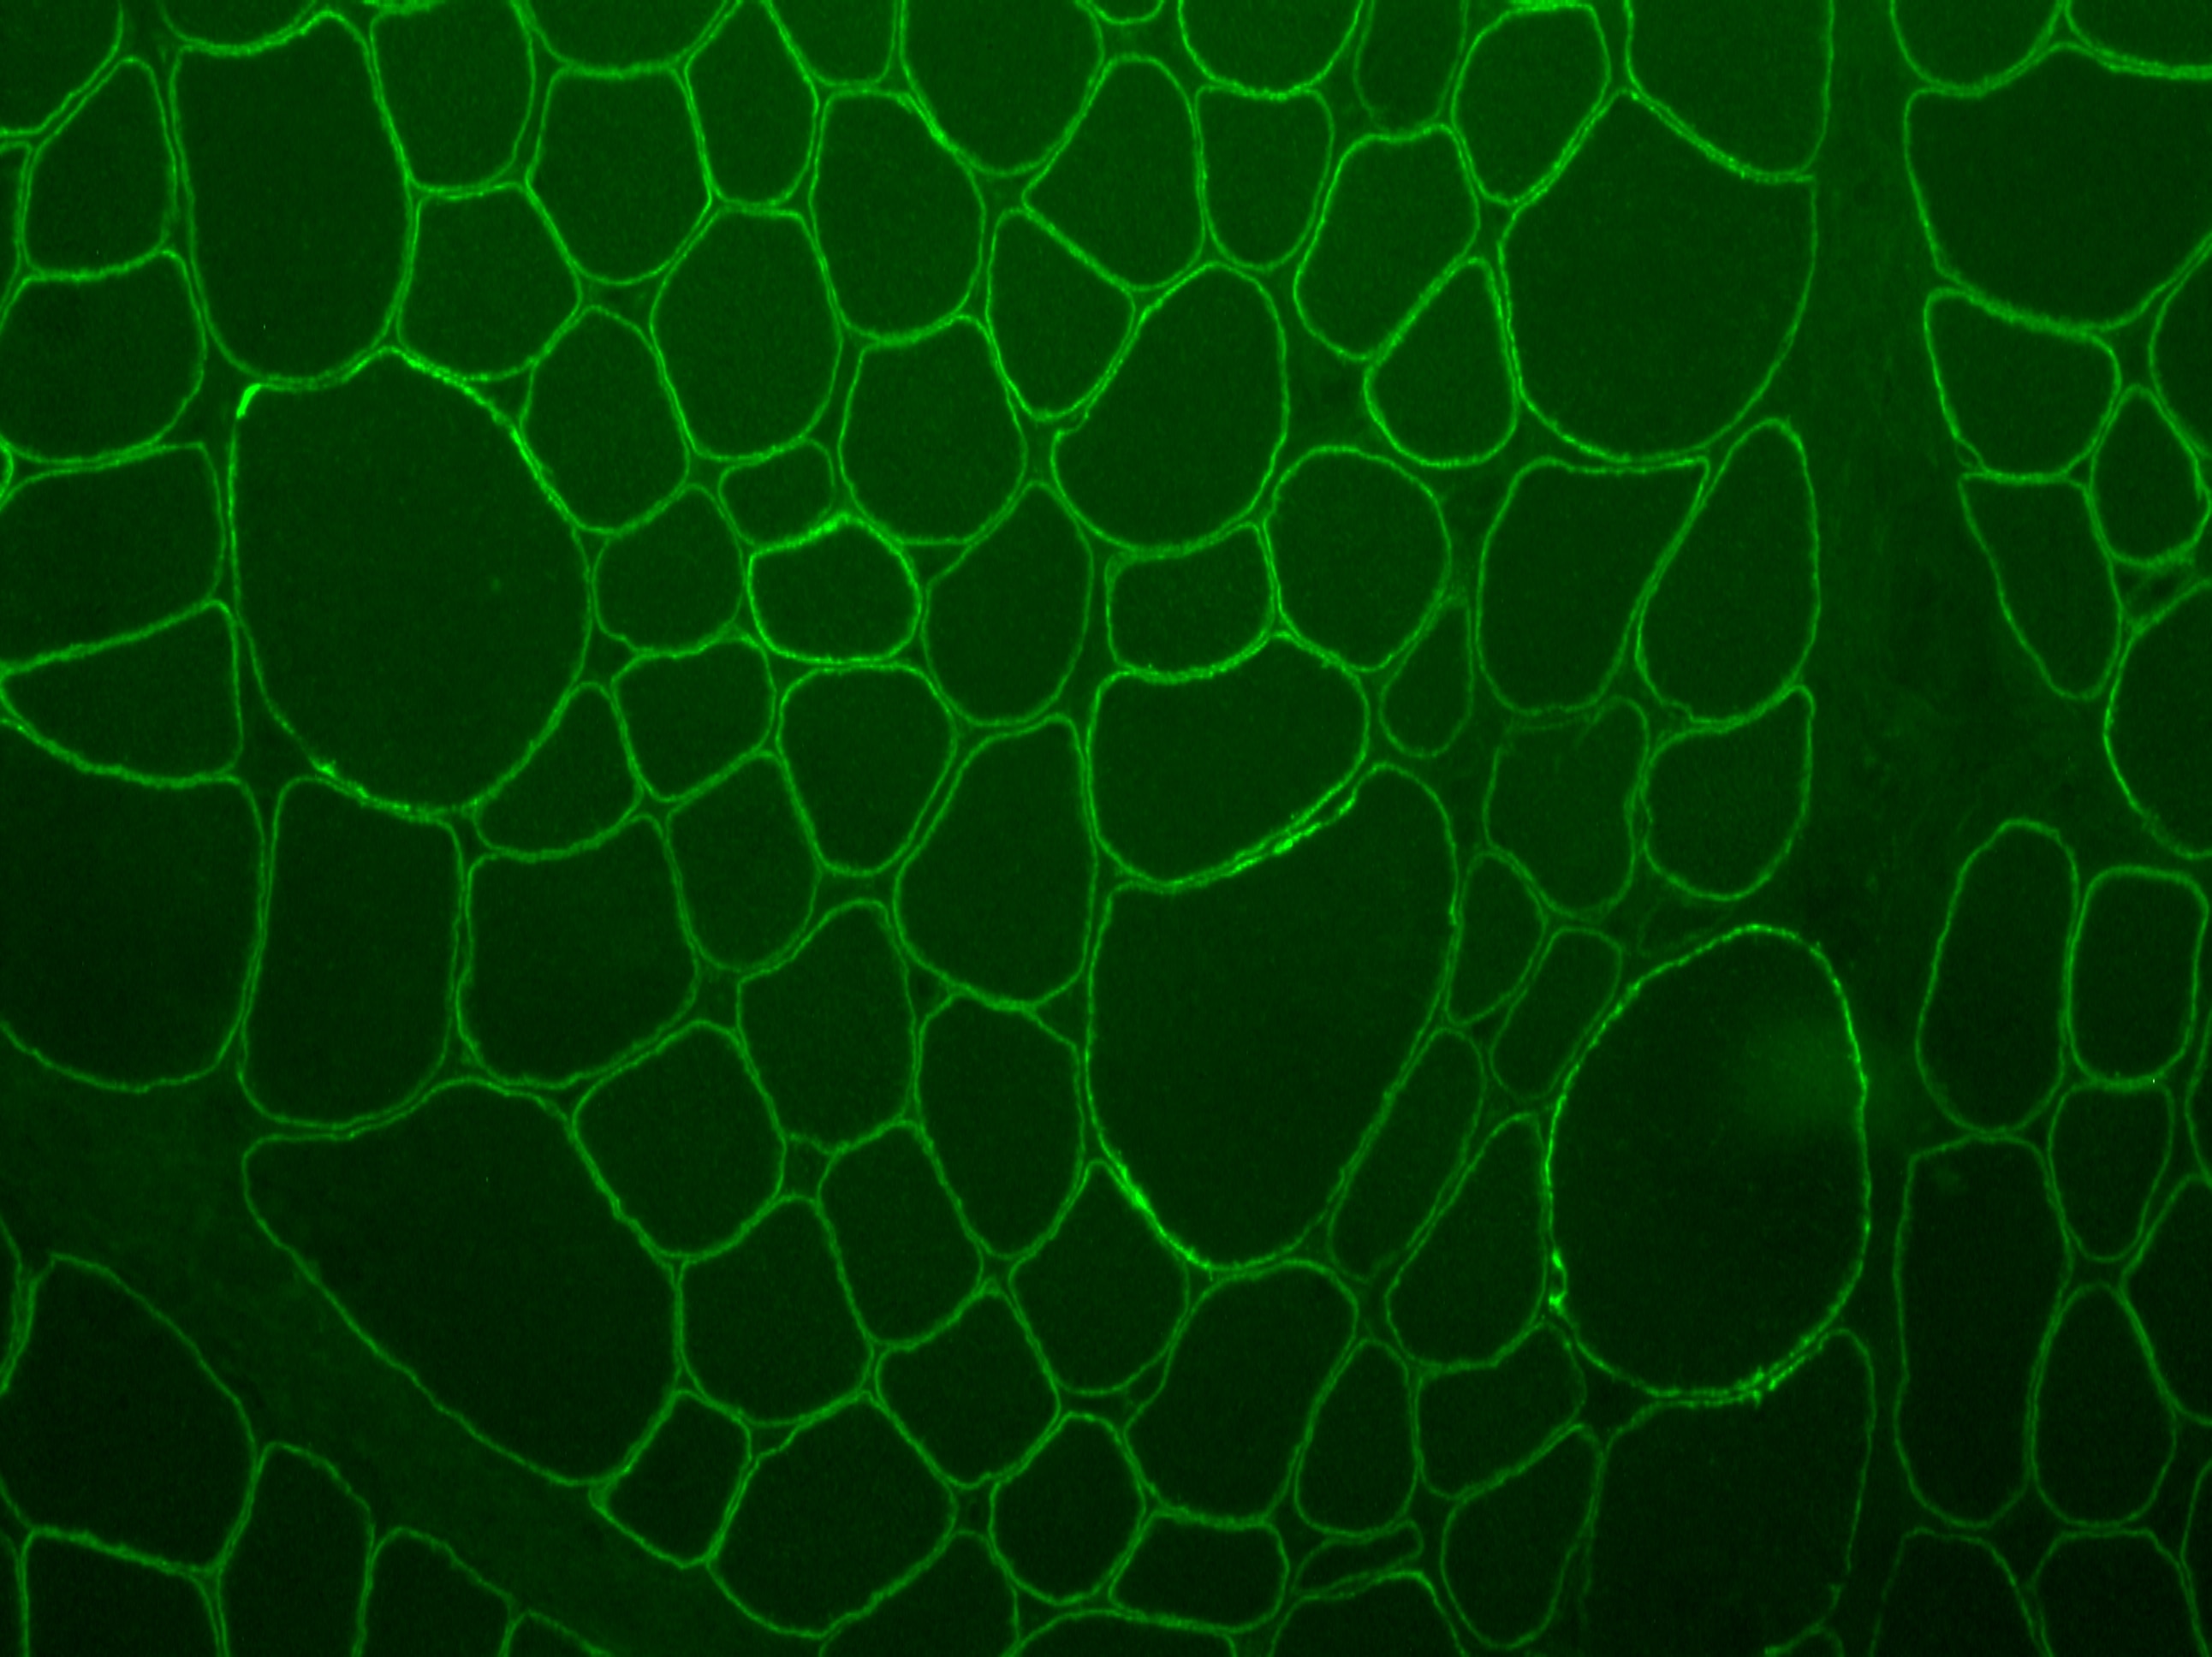

| Application Notes | ICC/IF Fixation Permeabilization: Use PFA/Triton X-100. Beta Sarcoglycan Antibody validated for IHC-Fr from a verified customer review. |

| Siemionow M, Cwykiel J, Heydemann A et al. Dystrophin Expressing Chimeric (DEC) Human Cells Provide a Potential Therapy for Duchenne Muscular Dystrophy Stem Cell Rev 2018-03-15 [PMID: 29546607] (ICC/IF, Human) | ICC/IF | Human |

Enlarge |

reviewed by:

Margherita verardo |

IHC-Fr | Human | 10/08/2019 |